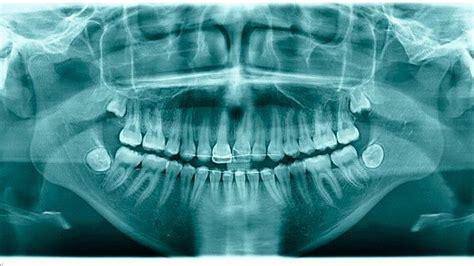

Wurzelkanalbehandlung

Die Behandlung eines nekrotischen Zahns beinhaltet in der Regel die Entfernung der abgestorbenen Pulpa und deren Ersatz durch Füllmaterial. Dieses Verfahren, die Wurzelkanalbehandlung, wird oft von einem Zahnarzt oder Endodontologen durchgeführt. Nach der Behandlung ist eine regelmäßige Überwachung erforderlich, um ein Wiederauftreten der Infektion zu verhindern.

Nach einem festen Schlag auf den Mund können sich Zähne lockern, zu wackeln anfangen oder verschoben sein. Vereinbaren Sie schnellstmöglich einen Termin bei Ihrem Zahnarzt oder besuchen Sie eine Zahnklinik. Eine spezielle Schiene, die an den Nachbarzähnen befestigt wird, stabilisiert den lockeren Zahn, damit er wieder festwachsen kann. Nach etwa zwei Wochen wird die Schiene entfernt, und eine Kontrolluntersuchung erfolgt sechs Wochen später.

Tief in den Kiefer gedrückter Zahn

Wenn ein Zahn nach einem Unfall tief in den Kiefer gedrückt wird, wird er nicht einfach herausgezogen. Der Zahnarzt befestigt eine mit Federn bestückte Schiene an den Nachbarzähnen. Sobald der Zahn sich wieder an seiner Ursprungsposition befindet, wird er erneut geschient. Diese Schiene verbleibt so lange, bis der Zahn sich wieder komplett gefestigt hat.

Riss im Zahn nach Unfall

Wenn Sie nach einem Zahnunfall feststellen, dass der Zahn einen Riss hat, gilt es herauszufinden, ob es sich lediglich um Schmelzrisse oder um eine Fraktur der Zahnkrone bzw. -wurzel handelt. Während ein Sprung oder Riss im Zahnschmelz keine weiteren Folgen nach sich zieht, können Zahnfrakturen, die bis zur Zahnwurzel reichen, im schlimmsten Fall zum Absterben des Zahnes führen. Die betroffene Person muss so schnell wie möglich in eine Zahnklinik oder kieferchirurgische Praxis gebracht werden.

Ankylose des Zahnes

Die dentale Ankylose ist eine seltene Komplikation, bei der die Zahnwurzel teilweise mit dem Knochen verschmilzt, der sie umgibt. Dies kann nach einem Zahntrauma, einer Entzündung oder genetischen Ursachen vorkommen. Der Zahn verliert seine physiologische Beweglichkeit.

Folgen und Behandlung der Ankylose

Bei Milchzähnen kann die Ankylose das Wachstum behindern und die normale Zahnentwicklung stören. Bei bleibenden Zähnen kann sie zu einem Höhenunterschied zu den übrigen Zähnen führen. Eine frühzeitige Diagnose und Behandlung kann funktionelle und ästhetische Probleme begrenzen. Eine kieferorthopädische Behandlung oder die Extraktion des Zahnes kann notwendig sein.